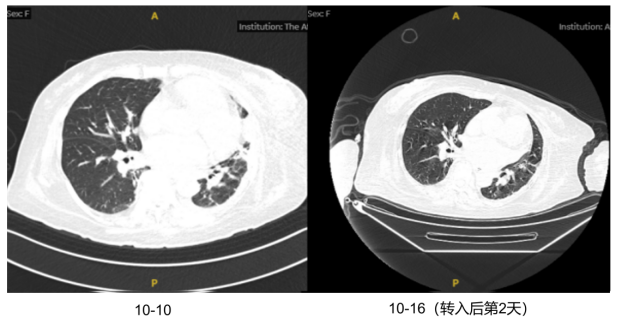

胸部CT(2023-10-10):两肺胸膜下多发片状斑片状高密度影,左肺部分实变,左侧少量胸腔积液1

1  胸部CT2023-10-10

1)感染性休克:患者反复发热,炎症指标明显升高,胸部CT提示两肺感染,SOFA评分>2分,伴血压下降。感染诱发病情加重可能性较大,迅速调整治疗方案,予比阿培南抗感染治疗,2天复查炎症指标白细胞降至19.8×109/L,中性粒细胞19.16×109/LCRP 77.4 mg/L,PCT 13.8 ng/ml。复查胸部CT发现,患者肺部感染程度不能解释其感染性休克的表现3,考虑可能合并其他部位的感染。患者结合胆红素140 U/L(占总胆红素的60%以上)明显升高考虑为梗阻性黄疸可能性大,及时完善腹部CT和彩超,报告:脾大,胰腺尾部密度不均匀,胆囊壁水肿、增厚,胆囊腔密度增高,管扩张4考虑胆囊炎并胆管炎继发感染性休克可能。2天加用替加环素50 mg q12h。

3  患者转入RICU后复查胸部CT